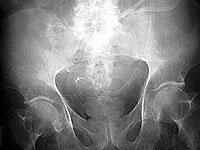

写真7は 72 歳、女性、糖尿病で卵巣腫瘍切除術後、胆摘後。

下行結腸と壁側腹膜の間の溝にカテーテル先端が固定されています。

普段、横になっていることが多いとこの位置にカテーテル先端が移動しますが、左下側臥位でバッグ交換すると注排液の異常は生じません。

写真8は上腹部へカテーテルが移動したときに長時間排液して大網がカテーテルにはまり込み腸管の動きでカテーテルが引き伸ばされています。

注排液ができなくなったためカテーテル交換をおこないました。